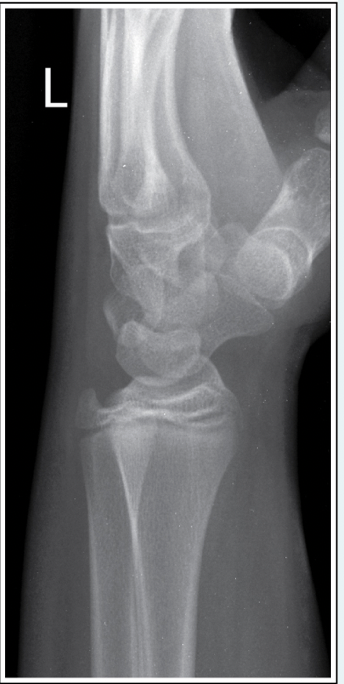

This AP elbow image demonstrates incorrect positioning of the part. What error occurred?

d.Humeral epicondyles are not parallel to the IR

How should this error be corrected on the repeat AP elbow image?

b.Arm should be rotated internally